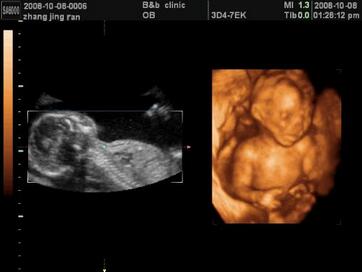

这是怀孕5个月胎儿四维彩超图

通过怀孕5个月胎儿四维彩超图可以看到宝宝还比较小,身上大概19—22厘米,体重350~400克,整体看上去小家伙的皮肤还是红红的,皮下脂肪还不是很多,看上去皱皱的。胎宝宝的眉毛和眼睑已经清晰可辨,10个小手指上也已长出了娇嫩的指甲。手部和手指的小动作多了起来,不是抓抓小鼻子、就是揉擦小脸、拍拍小脸蛋,有时还会撅撅小嘴。